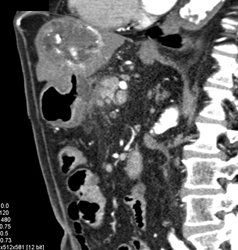

Liver Metastases From Bladder Cancer